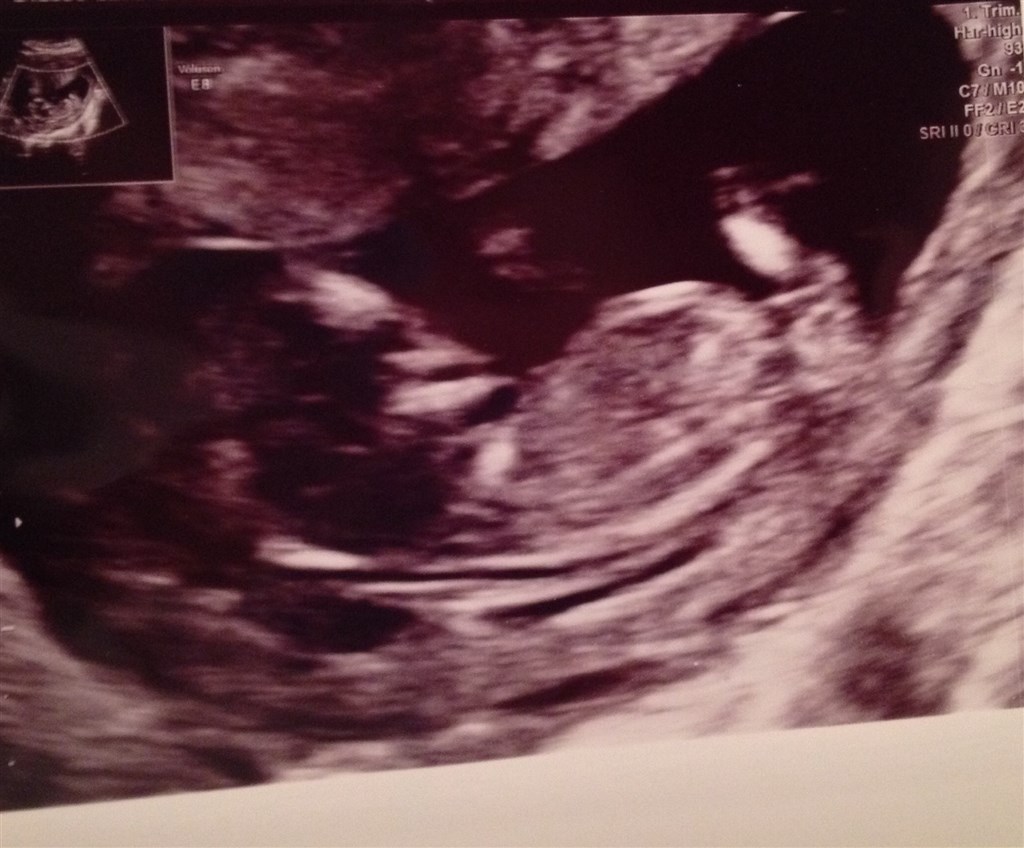

Ville blive rigtig glad hvis nogen ville komme med nogle bud på, hvilket køn der gemmer sig i min mave?

Billedet er fra NF, så jeg ved godt, at det endnu er tidligt

Det ville være et rent rent herfra. Både fordi, at billedet er fra NF og kønnet derfor ikke er tydeligt endnu, men også fordi, at billedet er fra siden af, og det derfor ikke til at se, hvad der gemmer sig imellem benene

Men som rent gæt, ville jeg sige pige

Og tillykke med det